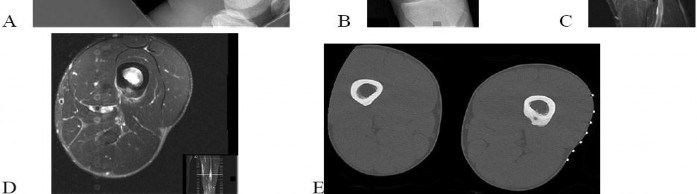

Question 15

A 28-year-old rugby player presents unable to actively flex the distal interphalangeal (DIP) joint of his ring finger after grabbing an opponent's jersey. Radiographs reveal a small bony avulsion fragment located at the level of the proximal interphalangeal (PIP) joint. According to the Leddy and Packer classification, what type of injury is this?

Explanation

Jersey finger represents an avulsion of the flexor digitorum profundus (FDP) tendon. Leddy and Packer classification: Type I involves retraction to the palm, both vincula ruptured (high risk of ischemia, requires urgent repair). Type II involves retraction to the PIP joint level, where it is held by the intact vinculum longus; a small bony fragment may be seen at this level. Type III involves a large bony avulsion that is caught at the A4 pulley (DIP joint level). This patient has a Type II injury.